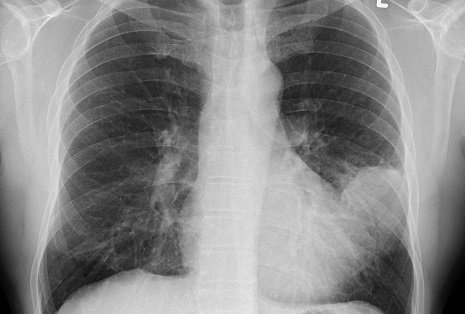

Zur Diagnose werden zuerst Anamnese, Inspektion und Auskultation (Abhorchen von Lunge und Herz) durchgeführt. Blutbild und Speichel werden auf Erreger hin untersucht. Das Röntgenbild zeigt einen „angeschwollenen“ Lungenbereich – hier in der Röntgenaufnahme links:

Abb1.: Röntgenaufnahme einer Lunge – Diagnose Lungenentzündung; zum Vergrößern auf das Bild klicken.